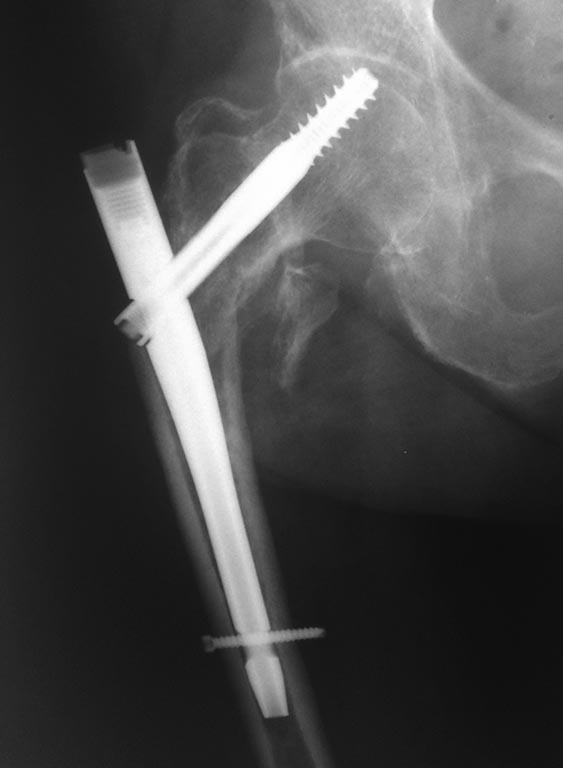

Коллеги, добрый день, прошу помочь в тактике лечения пациента!Пациентка В., 75 лет, без выраженной коморбидности, получила травму в августе 2014 года, диагностирован "Закрытый чрезвертельный перелом правой бедренной кости со смещением отломков", была прооперирована, выполнена закрытая репозиция, интрамедуллярный остеосинтез правой бедренной кости проксимальным бедренным штифтом. К сожалению, первичных снимков не предоставлено, имеются 2 снимка, через 1 месяц после операции, в сентябре 2014 и второй снимок, в январе 2015, пациентка на данный момент передвигается с помощью ходунков, отмечает болезненность при движениях и пальпации, объясняет - "Как-будто кость упирается в железку". Не хочется говорить о неправильной техники и cut-out и/или cut-through синдроме, интересно - что можно сделать и какую тактику лечения выбрать. Заранее благодарен.

Пока нет большой дыры в головке и впадине, надо сделать реостеосинтез. Аналогичный гвоздик, но уже в правильном положении. С остеотомией или без. Надо вторую проекцию хотя бы, а лучше бы еще и КТ.

Все-таки речь тут идет скорее о чрезподвертельном переломе, а не чрезвертельном. И не столько о неправильном введении винта, сколько о неправильном введении самого гвоздя непосредственно в дистальный отломок или его миграции через продольную линию перелома. Конечно нужна КТ. И, вероятно, длинная версия интрамедуллярного фиксатора.

Сделайте боковую проекцию, возможно отсутствует репозиция в передне-заднем направлении. Нередко бывает, что центральный фрагмент разворачивается кзади и шеечный винт мог быть введён в шейку и головку спереди назад ( при отсутствии контроля боковой проекции во время операции)

Снимок плохого качества, правда